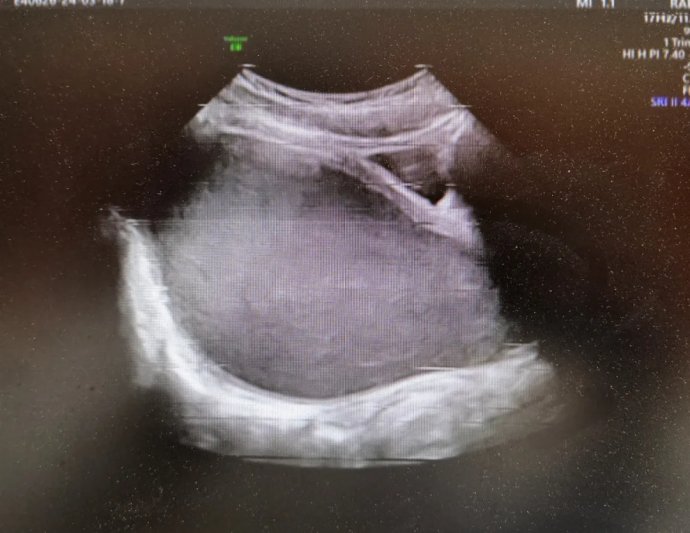

12歲花季少女出現(xiàn)周期性下腹痛,在其父母帶領(lǐng)下先后就診咸陽市兩家醫(yī)院,最終,她們選擇了延安大學(xué)咸陽醫(yī)院婦科。就診當(dāng)日,趙倩蘭主管醫(yī)生詳細(xì)追問病史,患者自訴已間斷性下腹痛3月余,本次腹痛較前明顯加重,腹痛難忍。入院后醫(yī)生立即為其安排了婦科彩超及盆腔磁共振,發(fā)現(xiàn)該患者宮腔、宮頸及陰道上段充滿大量積血,積液壓迫膀胱及直腸,導(dǎo)致排便、排尿障礙。張素寧主任為其查體后發(fā)現(xiàn),該患兒陰道竟無開口,導(dǎo)致經(jīng)血無法排出,閉鎖處無隆起,無青紫,排除處女膜閉鎖,直腸檢查發(fā)現(xiàn)陰道上端有一包塊凸向直腸,包塊下緣距離肛門口約4-5cm,結(jié)合查體及相關(guān)輔助檢查,考慮該患者為陰道閉鎖,值得慶幸的是該患者其他系統(tǒng)暫未發(fā)現(xiàn)畸形。

婦科超聲圖